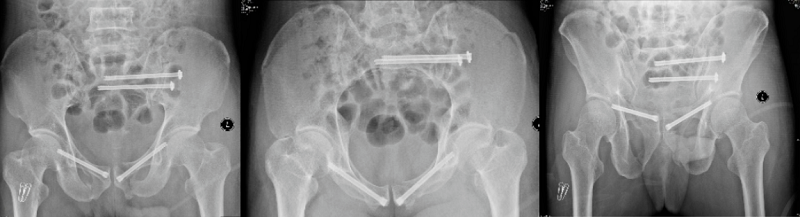

手術中

術后X線片

在本次科研臨床試驗中,全部22例骨盆骨折病例均順利完成了微創(chuàng)的閉合復位,驗證了智能化骨折復位機器人系統(tǒng)的術前自動手術規(guī)劃、術中實時3D導航及力位協(xié)同控制等創(chuàng)新功能的臨床適應性和安全性,系統(tǒng)操作順暢,操作精度和穩(wěn)定性滿足臨床需求,取得了良好的療效。